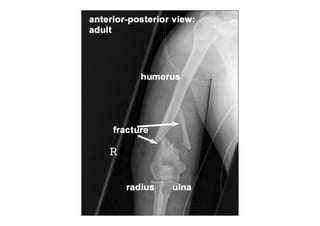

2- Radiologia do Trauma Esquelético (Radiografias)

RADIOLOGIA DO

TRAUMA DO ESQUELETO

Referência: http://www.accessexcellence.org/RC/VL/

figura